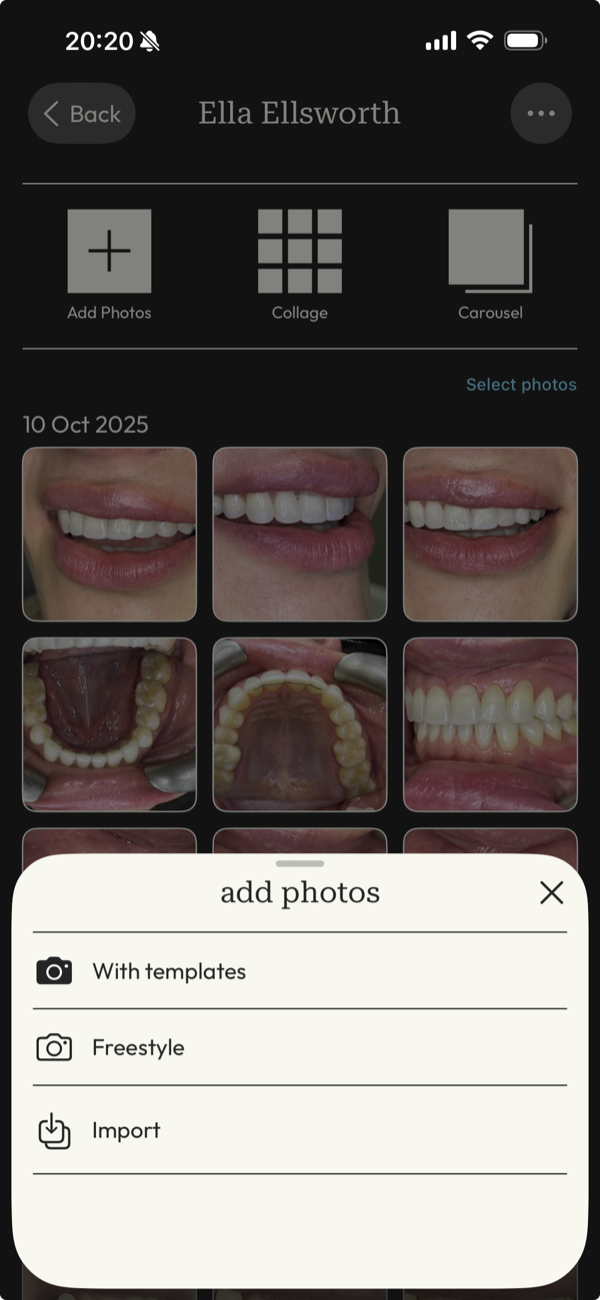

Capture, organise, and present dental photos with built-in patient consent tracking.

picture perfect images

Capture images with guided precision or import your DSLR work, then transform them into flawless before-and-after cases ready to present and share.

all your photos in one place

Manage your portfolio effortlessly from your phone, and sync with other devices for optimised, up-to-date images, organized by patient and date.

Give clients confidence and clarity in the moment with intuitive tagging that makes images just a tap away whenever you need them.